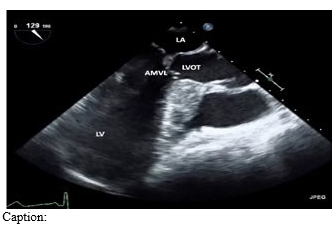

HCM can lead to hypertrophy of different parts of the left ventricle. While the basal-septal region is most commonly affected, the apex, free wall, and postero-lateral wall may be affected as well [13]. The right ventricle is rarely involved. LVOTO may occur from asymmetrical hypertrophy of the interventricular septum inferior to the aortic valve (which was why HCM was previously called hypertrophic subaortic stenosis), or from systolic anterior motion (SAM) of the mitral valve. Narrowing of the left ventricular outflow tract (LVOT) leads to increased velocity of blood flow.

This creates drag forces and a Venturi effect on the mitral leaflets. The increased velocity of blood causes reduced pressure in the LVOT, and the lower pressure draws the anterior mitral leaflet (AML) into the LVOT. This displacement of the AML during systole worsens LVOTO and is referred to as SAM (Systolic Anterior Motion of the mitral leaflets). SAM of the anterior leaflet also disrupts the coaptation of the mitral valve leaflets, and often results in mitral regurgitation. The result is a dynamic obstruction that varies with cardiac contractility, preload, and afterload. Microvascular dysfunction couples with the cycle of worsening hypertrophy and obstruction, predisposing HCM patients to myocardial ischemia and heart failure [14].

Figure 1: LAX view of septal hypertrophy and SAM, resulting in LVOTO during ventricular systole.